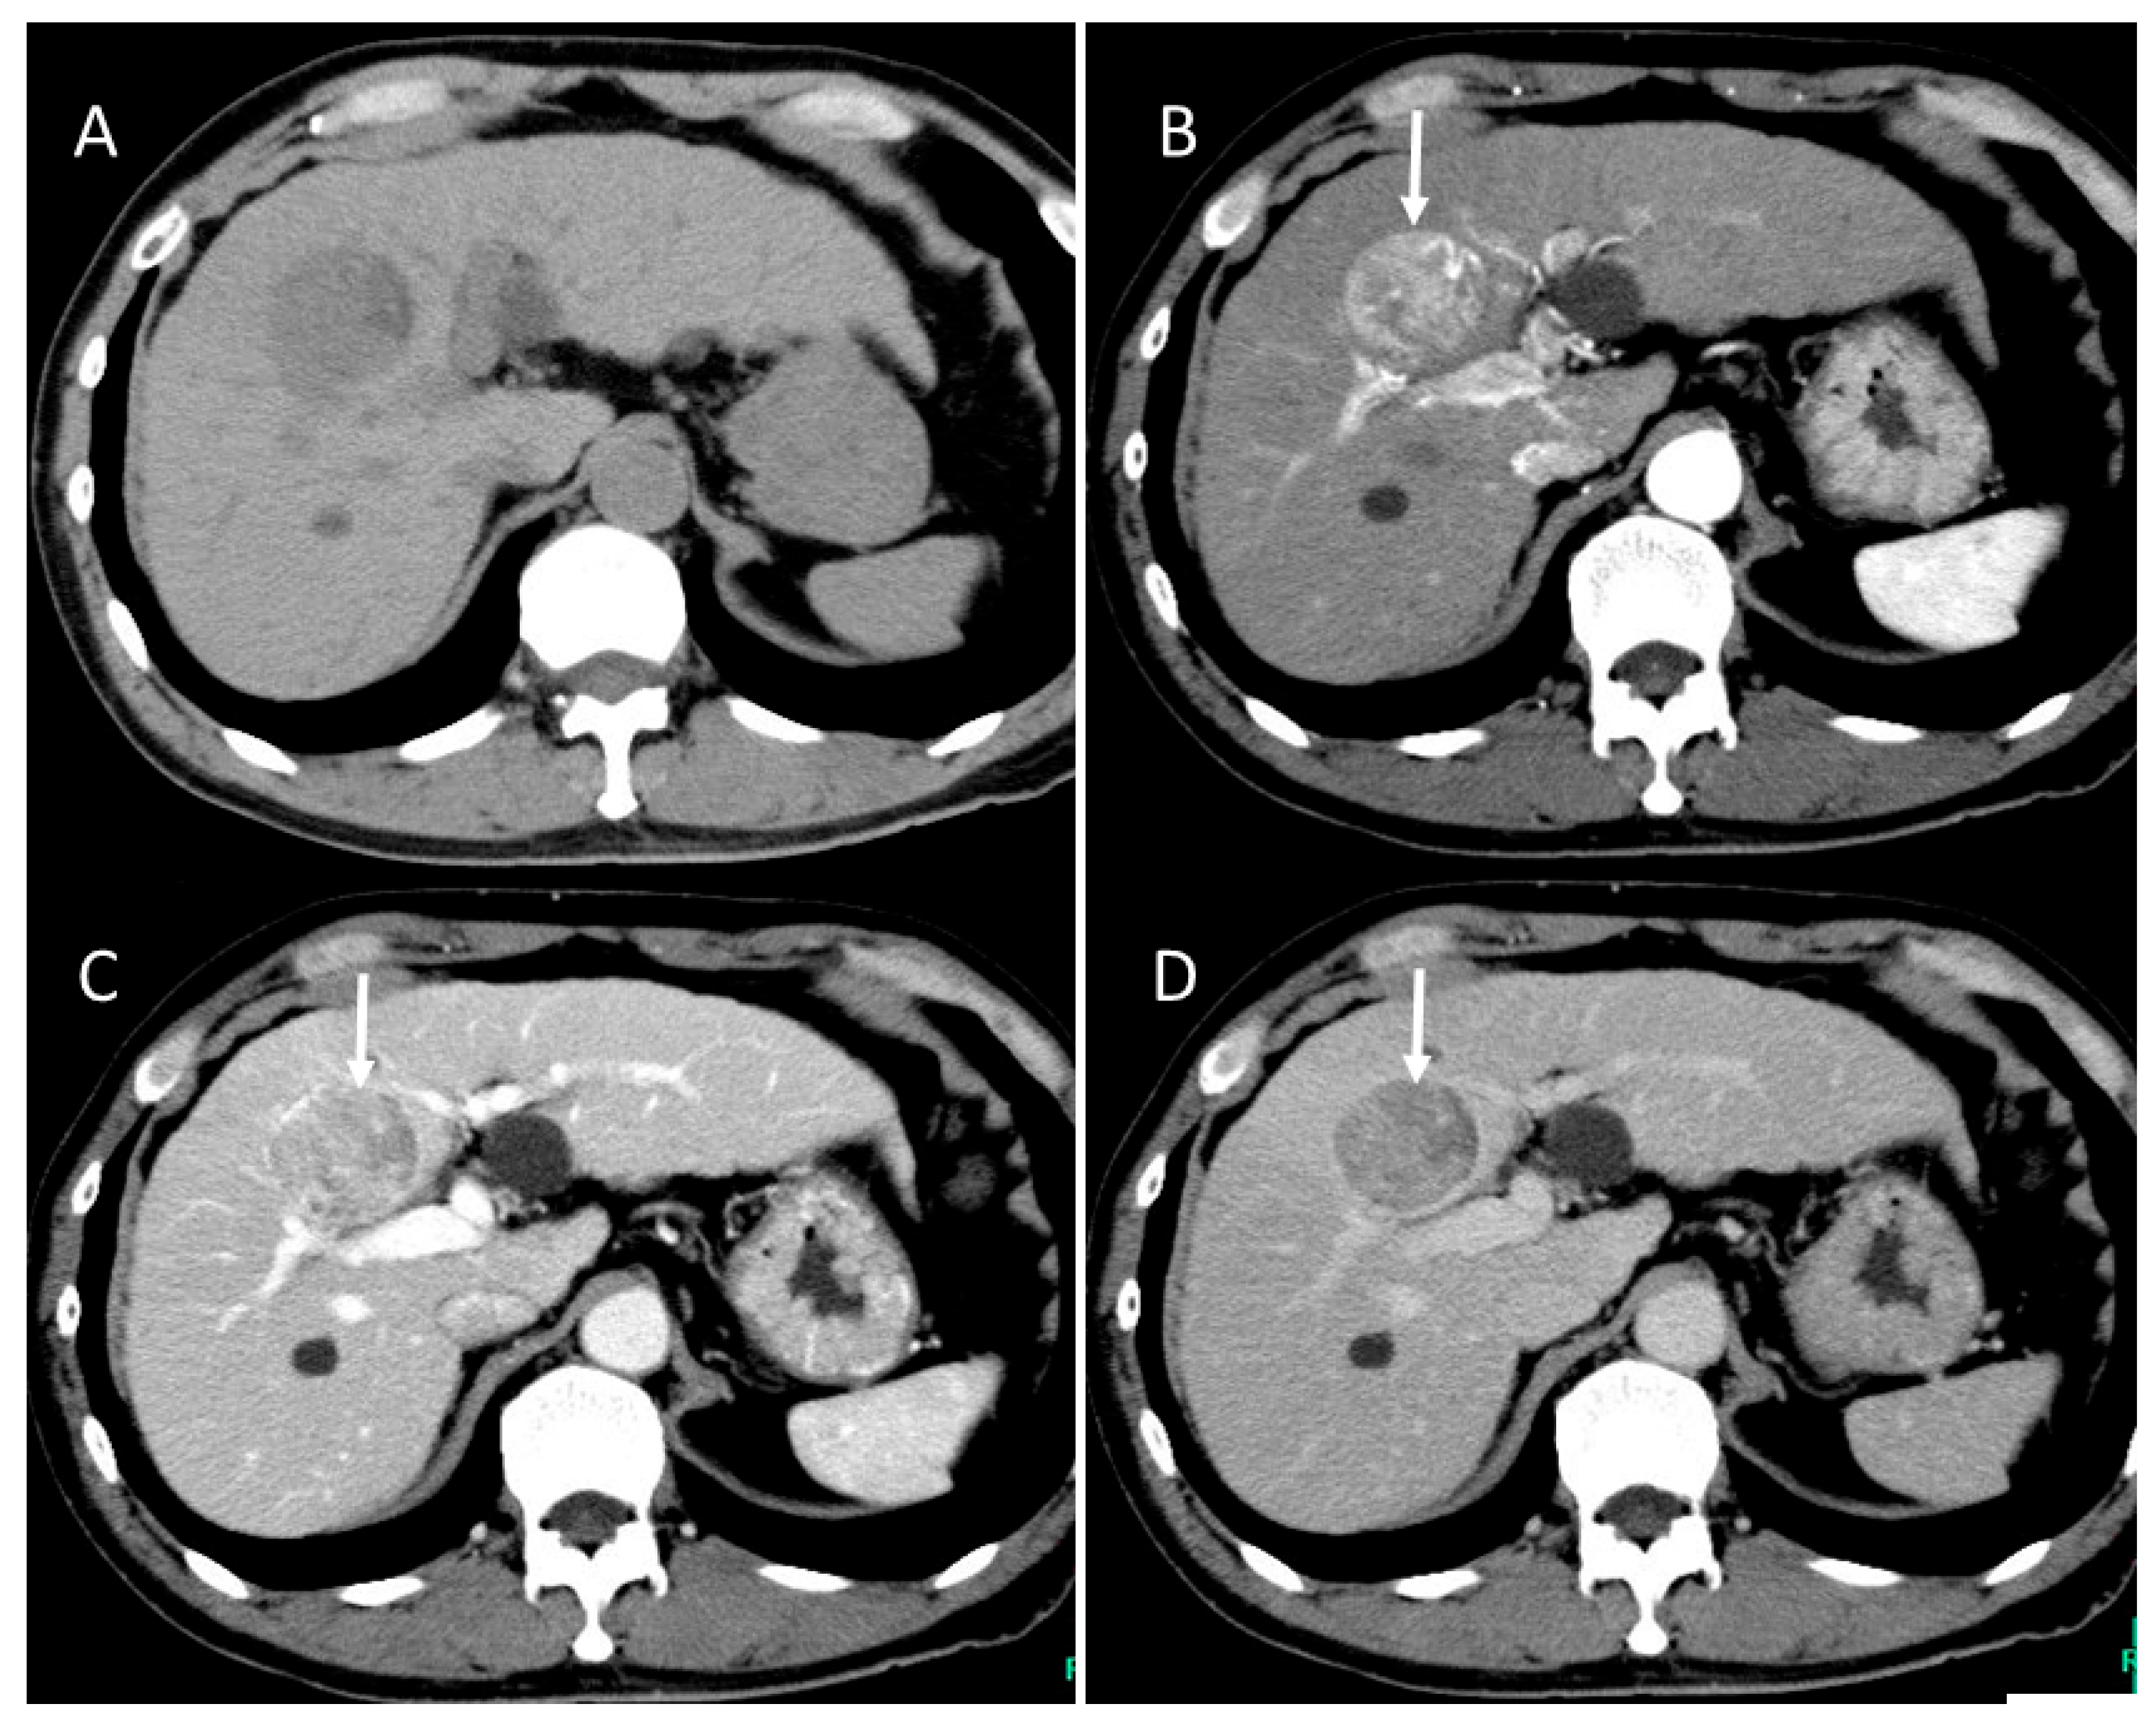

4.4. Moderately Differentiated Hepatocellular Carcinoma (Moderately HCC)

4.5. Poorly Differentiated Hepatocellular Carcinoma (Poorly HCC)

4.6. Fibrolamellar Hepatocellular Carcinoma (FL-HCC)